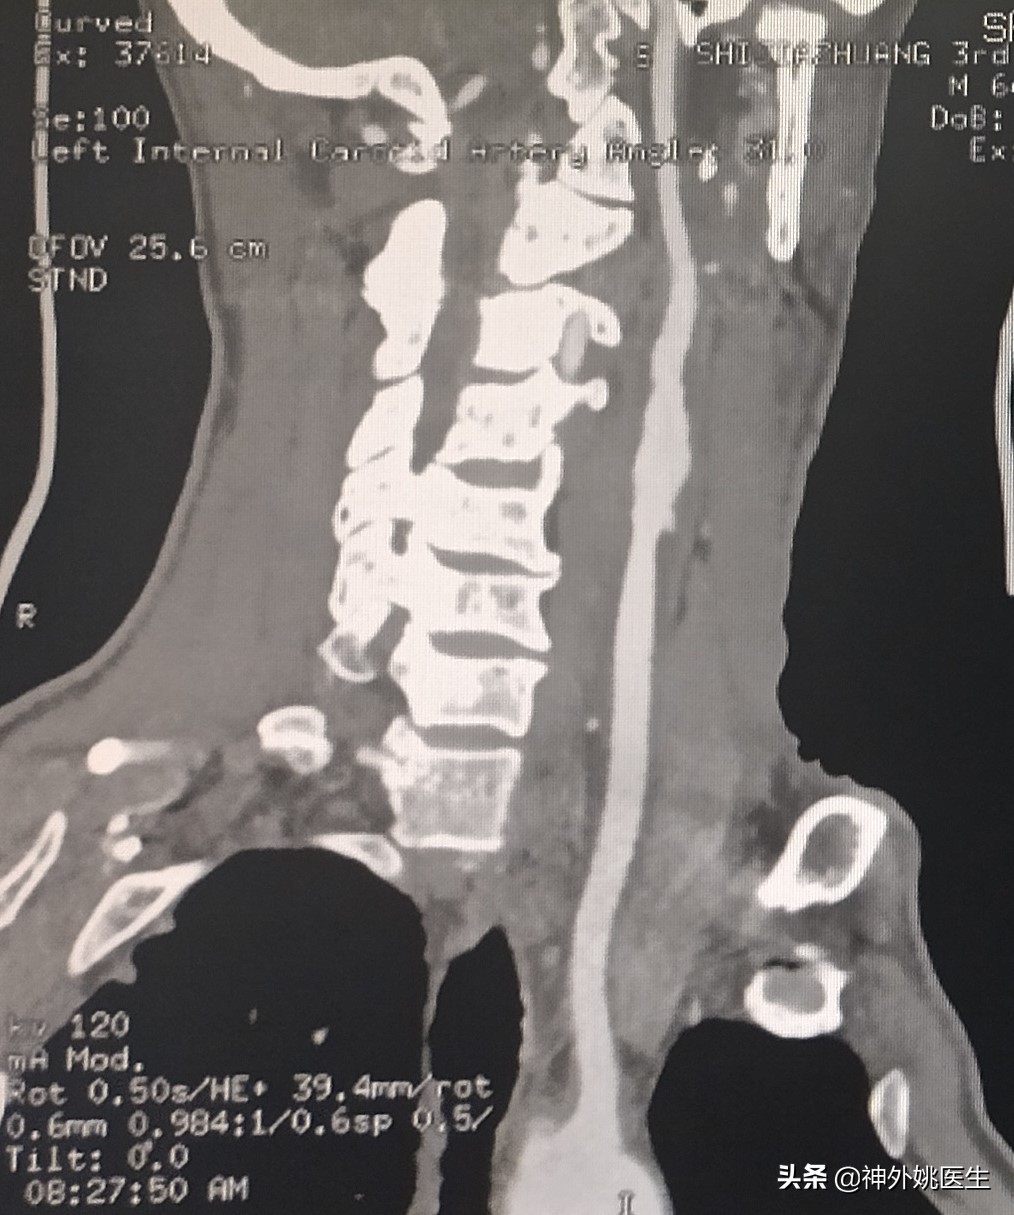

患者廉XX,男性,64岁。主因头痛、头晕,伴右侧肢体无力半年,加重2个月入院。既往“肺腺癌”病史3年,行靶向药物治疗。无“高血压、糖尿病、慢性胃炎”病史。1年前行“腰椎椎体成形手术”。查体:Bp124/91mmHg 神清,语利。双瞳孔正大等圆,对光反射灵敏。左侧肢体肌力5级,右侧肢体肌力5-级。双侧Babinski's征(-)。脑血管彩超示:双侧颈动脉内膜增厚伴斑块形成(多发),左侧颈内动脉起始部狭窄(79-99%)。头MRI+MRA检查:1.双额顶叶及右基底节区缺血灶。2.右颈内动脉虹吸段开窗畸形;左大脑前动脉A1段稍纤细。(图1)颈椎CT示:1、颈椎多发异常密度影,考虑转移瘤;2、颈5/6椎间盘左后突出,椎管狭窄;颈椎骨质增生,排列不稳;4、项韧带钙化。颈部MRI+MRA检查示:1、颈3/4、4/5、5/6、6/7椎间盘突出。2、颈3/4、6/7水平水平椎管狭窄。3、颈椎骨质增生。4、左侧颈内动脉起始部狭窄。(图2)

图2 颈部MRA示左侧颈内动脉起始部狭窄。